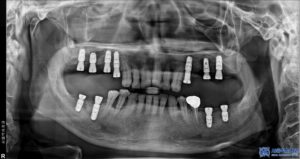

이번에 저희 서울박사치과를 찾아주신 환자분께서는

기존에 다른 치과에서 임플란트 치료를

받으셨었지만, 기존 임플란트와 보철물이

파절되면서 다시 진단을 받아보고자

저희 치과에 내원하셨습니다.

우선, 환자분의 상악 오른쪽 어금니들은

치주 염증이 심한 상태로,

기존에 받으셨던 보철물 아래로 염증이

심하게 퍼져 제거가 필요한 상태였습니다.

뿐만 아니라, 상하좌우 맨 안쪽 어금니들의

잇몸과 뼈 상태가 많이 악화되어 있어

보존이 어려운 상황이었기에

각각 발치도 진행되어야 했습니다.

발치를 진행한 후, 우선적으로 하악 좌우 어금니

부위부터 무절개 임플란트를 총 4개 심었습니다.

이 과정에서는 뼈 이식도 병행하였습니다.

이후 상악 좌우도 순차적으로 치료를 진행하였으며,

기존 타 치과에서 심은 왼쪽 위 작은 어금니 위치의

임플란트와 파절된 인접 보철물도

함께 제거하였습니다.

상악 좌우는 모두 뼈이식을 동반한

무절개임플란트를 총 6개 식립하였습니다.